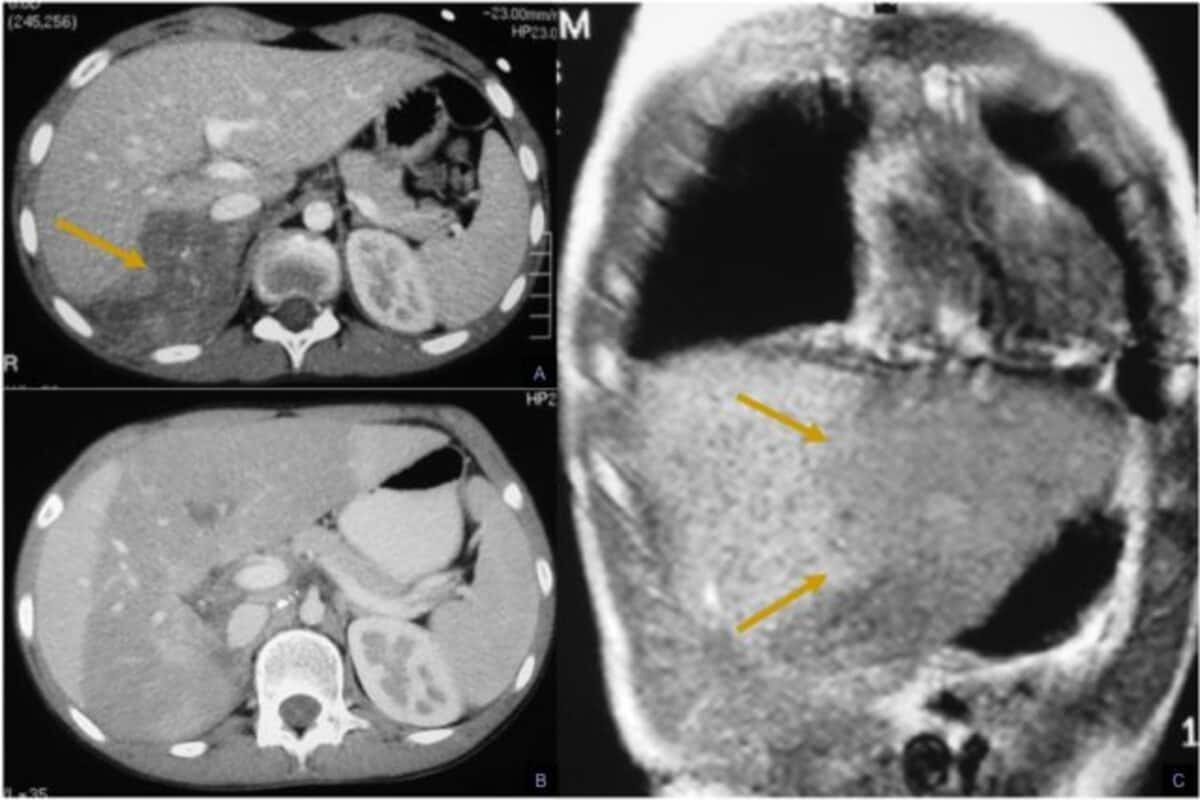

• УЗИ брюшной полости, КТ и МРТ;

• позитронно-эмиссионная компьютерная томографииюя (ПЭТ-КТ).